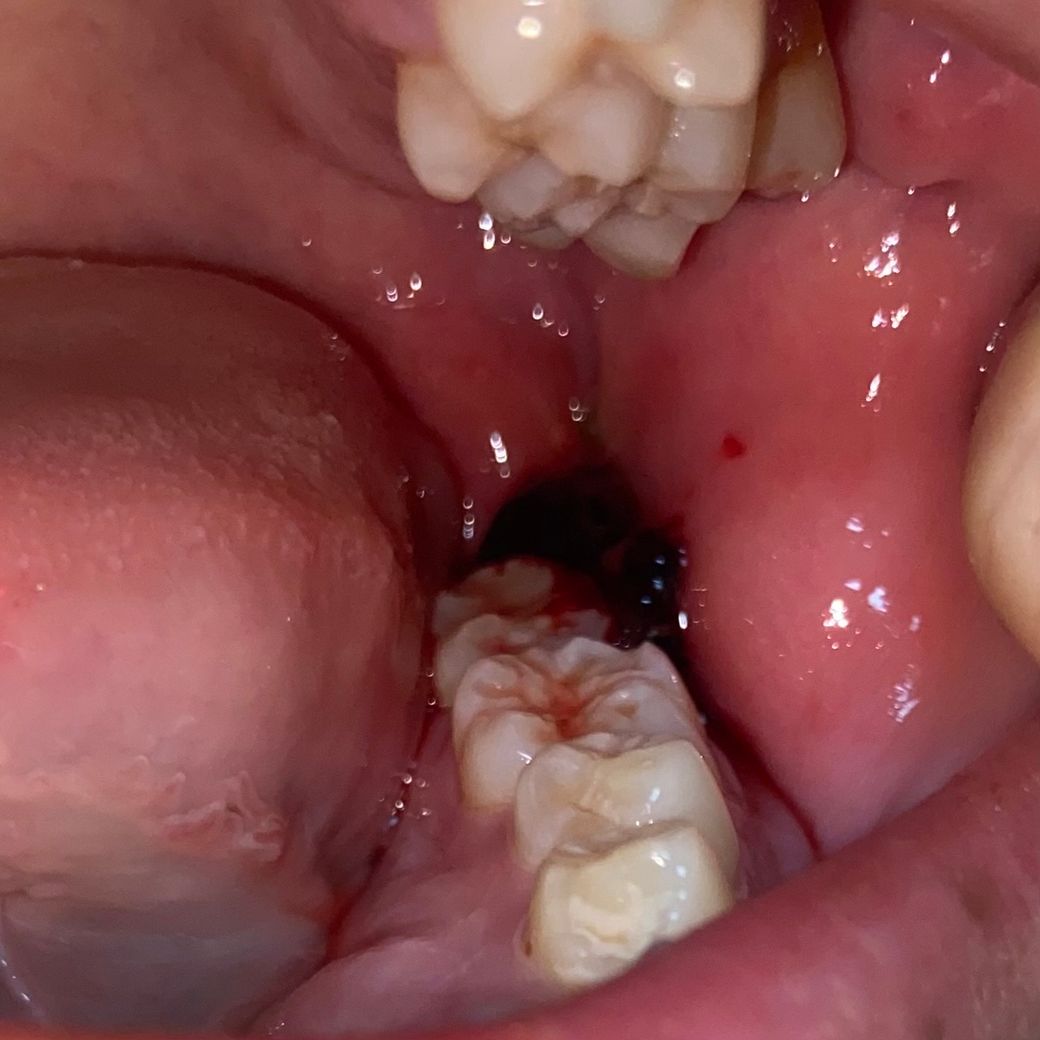

• 3번 째 사진

지난주 토요일에 발치했고 마지막 사진이 현재입니다 잘 낫고있는지 궁금해요... 어제 소독은 받았습니다. 근데 꼬맨 부분이 좀 땡기는데 이것도 맞나요

사진 시야각이 명확하지 않으나 발치한 곳에서 염증성 삼출물이나 농루는 보이지 않는 것 같습니다.

만약 치유에 이상이 있다면 어제 소독할 때 적절한 조치가 이루어졌을 것입니다.

너무 걱정하실 필요 없고 해당 부분 조심스럽게 위생 관리 해주시면 되겠습니다.

치유는 정상적으로 이뤄지고 있고 소독시 별말 없었으면 괜찮은겁니다 좀 땡기는 느낌은 치유과정 중 있을 수 있습니다